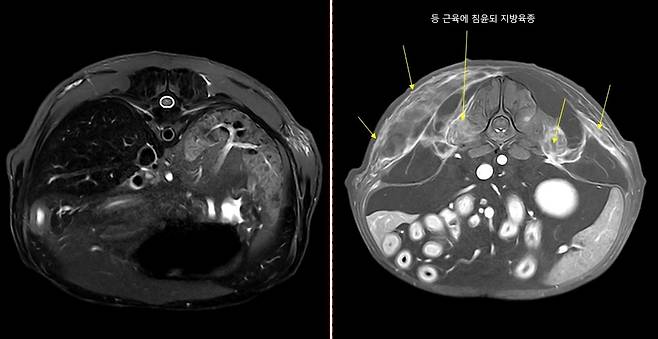

MRI로 지방육종 발견하는데 결정적 역할 하기도

최근 월드펫동물메디컬센터에서는 수의계에서 보기 드문 사례를 발견했다. 다른 병원에서 디스크 의심으로 의뢰된 환견의 MRI 영상에서 예상과 달리 전혀 다른 병변이 보였던 것. 안 실장은 촬영 범위를 바꿀 수 있도록 도왔고, 수의사가 지방육종 진단을 내리는데 결정적 역할을 했다.

그는 "국내에서 MRI로 동물의 지방육종을 발견한 사례는 보지 못했다"며 "매우 정교한 기술이 필요했는데, 환자가 제때 수의사에게 진단받고 치료를 이어갈 수 있어 뿌듯하다"고 말했다.